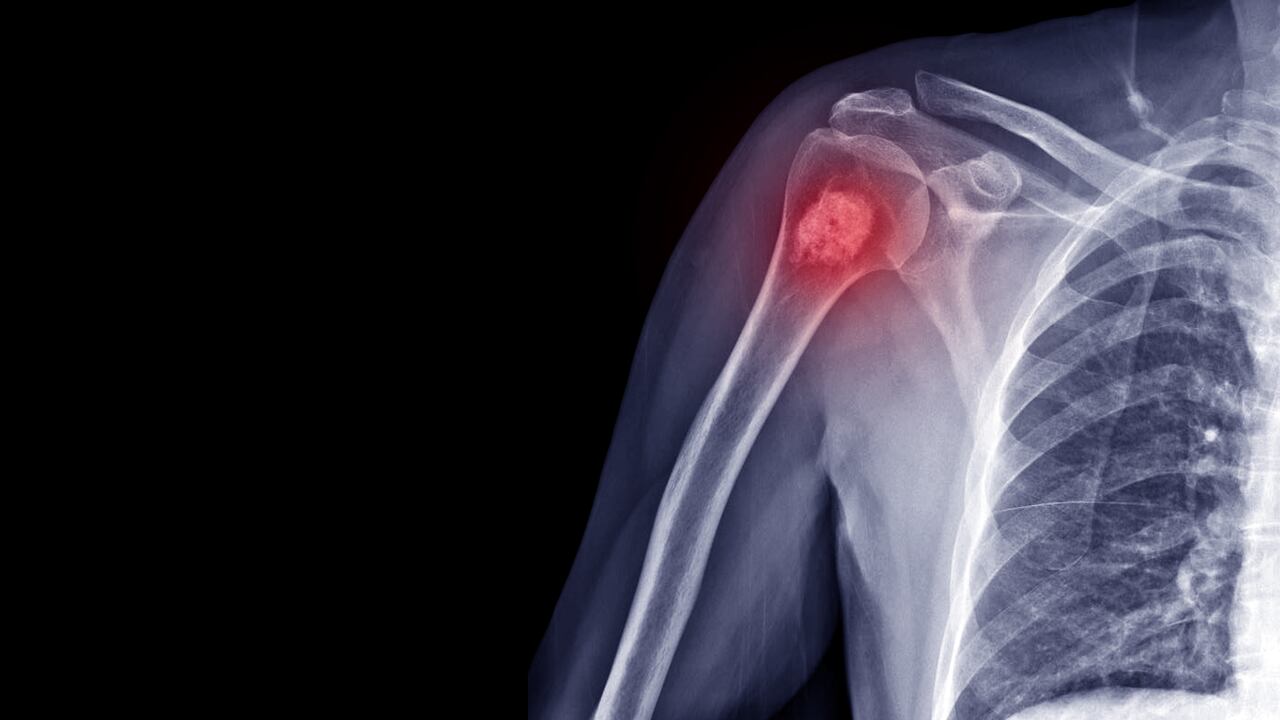

Fortalecer los huesos es crucial por varias razones importantes que afectan la salud general y el bienestar a lo largo de la vida, pues proporcionan estructura al cuerpo, protegen órganos vitales, permiten el movimiento y almacenan minerales esenciales, explica el portal especializado en salud Mayo Clinic.

Por esta razón, mantener huesos fuertes no solo asegura que estos órganos estén bien protegidos contra lesiones, sino que también aporta significativamente al movimiento y equilibrio del cuerpo, ya que son puntos de anclaje para los músculos, lo que a su vez reduce el riesgo de caídas y fracturas.

Los huesos almacenan minerales como el calcio y el fósforo, que se liberan según sea necesario para mantener el equilibrio mineral del cuerpo, lo que ayuda a mantener la salud general. Todo esto hace que al mantenerlos sanos y fuertes, contribuya a prevenir enfermedades como la osteoporosis, que aumenta el riesgo de fracturas y puede afectar la calidad de vida.